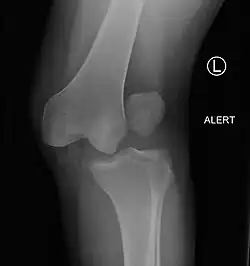

| Plain lateral X-ray of the left knee showing a posterior knee dislocation[1] | |